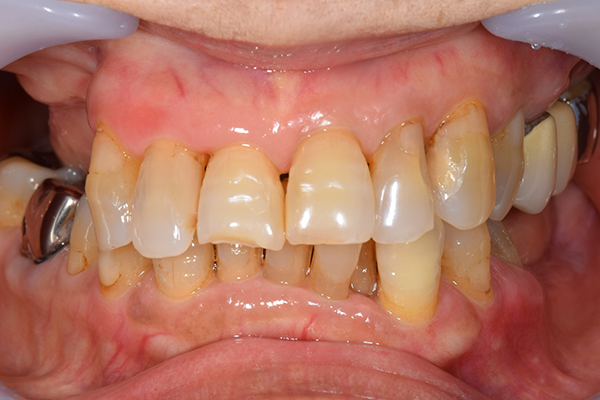

インプラント部以外にも歯周病が進行していましたので、歯周病の治療を行いました。 残念ながらインプラントと、1本の歯が残せなかったため抜歯を行いました。 その後、前歯の出っ張りを修正することと入れ歯の安定を図るため、残っている歯を全てかぶせ物にしていくことになりました。 写真中央は抜歯後に入れた治療用の入れ歯になります。 抜歯後歯ぐきが安定しましたら、入れ歯とかぶせ物の型取りを行いました。

噛み合わせチェックでしっかり奥歯で噛めるようにし、 歯を並べます。 その後、それに合わせて前歯を作っていきます。

こちらが完成したかぶせ物と入れ歯です。かぶせ物にはアタッチメントをつけて金属のバネが見えない構造になっています。 入れ歯自体も金属を使用して、極力違和感がでないように、薄く作成しました。

お口の中に入れた状態です。 非常に見た目もよい出来となりました。 バネがみえないと見栄えが全然ちがいます。